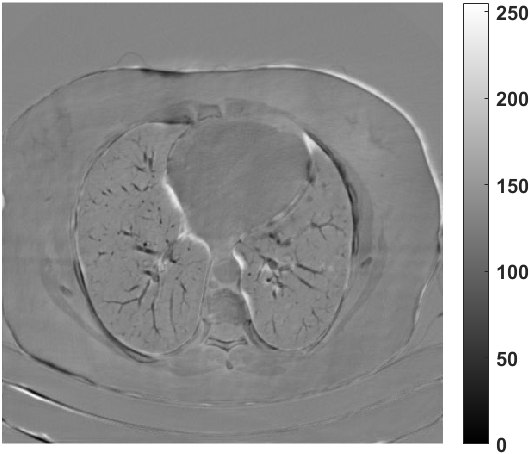

Fig. 4 presents the reconstruction results and residual images obtained by different methods for limited-angle reconstruction. As can be seen, the learning-based methods outperform the direct method and TV model, which exhibit serious artifacts in the missing angle region. Although the denoiser introduced by the FBP-Unet can somehow deal with the noises, the result still presents obvious artifacts. Compared to the SIPID, PD-net and FSR-nets, our LRIP-net1/2 can better preserve the image details and edges with less information left in the residual images. Thus, both the quantitative and qualitative results confirm that the low-to-high double-resolution strategy can improve the reconstruction accuracy for the limited-angle reconstruction problem.

We observe that the low-resolution image prior plays an important role in our method. More specifically, we compare the results of our LRIP-net with respect to different low-resolution priors, which are obtained by down-sampling rate of 1/2, 1/4, and 1/8, respectively. As can be seen in Table III, the best reconstruction results are obtained with the image prior reconstructed by the down-sampling rate of for 150∘, 120∘ and 90∘ limited-angle reconstruction. The visual comparison based on different image priors are also provided in Fig. 5, where obviously less artifacts are left in the reconstruction image by LRIP-net1/8. By comparing the running time, it is easy to see that the smaller the low-resolution image prior, the faster the LRIP-net works.